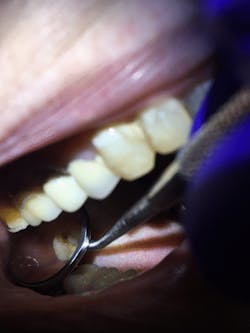

During my next visit with my mom, I performed oral hygiene with special attention to No. 2. I applied the silver diamine fluoride solution and followed it with the potassium iodide solution (figures 1 and 2). It was simple because I used the same technique as I would when applying fluoride varnish and with the caution of disclosing solution.

Figure 1: No. 2 prior to the Riva Star application

Figure 2: No. 2 after the application of Riva Star silver diamine fluoride and potassium iodide solution. Note the creamy white precipitate from the potassium iodide solution.